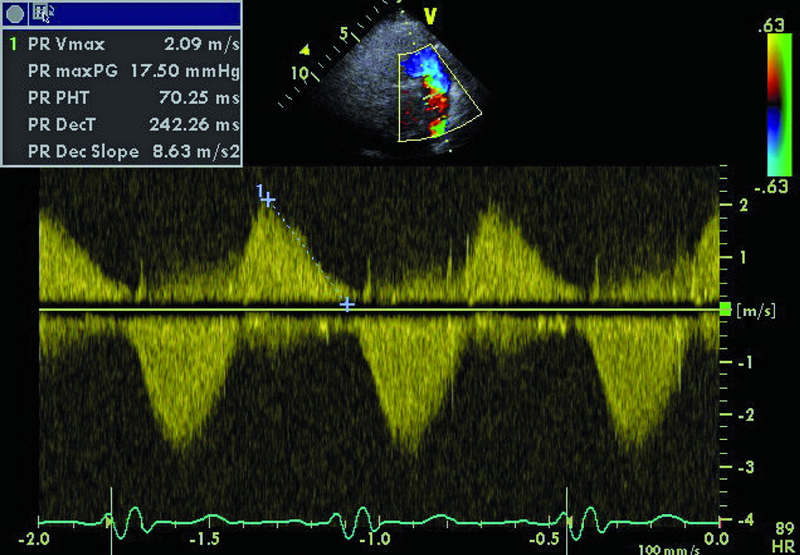

Droga odpływu prawej komory u opisanego chorego jest szeroka i z pewnością nie stanowi zapory dla przepływającej krwi (ryc. 1). Częstym powikłaniem całkowitej korekcji tetralogii Fallota, zwłaszcza z wykorzystaniem łaty przezpierścieniowej, jest duża niedomykalność zastawki płucnej, którą stwierdzono również u opisanego chorego. Strumień niedomykalności w badaniu kolorowego doplera jest szeroki i pokrywa prawie cały przekrój drogi odpływu (ryc. 2). Niedomykalność zastawki płucnej trudno ocenić ilościowo za pomocą techniki ultradźwiękowej. Złotym standardem diagnostyki jest rezonans magnetyczny, który pozwala określić tzw. frakcję niedomykalności. Spośród parametrów echokardiograficznych najbardziej zbliżonym i dość wiarygodnie odzwierciedlającym stopień niedomykalności zastawki płucnej jest czas połowicznego zmniejszenia gradientu ciśnień między pniem płucnym a prawą komorą (pressure half time, PHT). PHT krótszy niż 100 ms świadczy o istotnej niedomykalności zastawki płucnej (ryc. 3). Innym, nieanalizowanym w ilustracjach parametrem może być tzw. indeks niedomykalności, czyli iloraz czasu trwania fali zwrotnej płucnej do czasu trwania rozkurczu. Niedomykalność zastawki płucnej, nawet tak duża, jak w opisanym wypadku, nie musi istotnie ograniczać tolerancji wysiłku. W takiej sytuacji obowiązuje jednak precyzyjna ocena wielkości i funkcji prawej komory serca. Stopień powiększenia prawej komory u tego chorego jest umiarkowany (ryc. 4), a funkcja kurczliwa mięśnia mierzona za pomocą prędkości skurczowej ruchu bocznej części pierścienia trójdzielnego (S’) jest prawidłowa (ryc. 5). Dodatkowym parametrem łatwym do uzyskania niezwykle czułym w określaniu niedomogi prawej komory jest pole prawego przedsionka. Niewielkie przekroczenie górnej granicy normy, czyli 18 cm2, rejestrowane w tym przypadku (ryc. 6) potwierdza słuszność wyboru strategii zachowawczej. Chory może być nadal obserwowany, chyba że warunki anatomiczne drogi odpływu prawej komory pozwalają na przezcewnikową implantację zastawki Melody lub Edwards-Sapien. Określenie możliwości przeprowadzenia tego rodzaju interwencji ponownie wymaga jednak odniesienia się do wyników rezonansu magnetycznego lub wykonania cewnikowania serca.